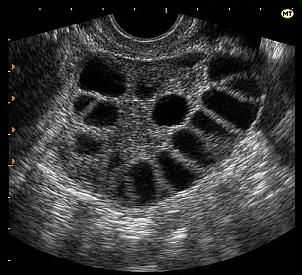

Синдром гиперстимуляции яичников (СГЯ) — редкое ятрогенное осложнение после стимуляции яичников (искусственная овуляция) с помощью вспомогательных технологий репродукции и других методов лечения бесплодия.

Симптомы СГЯ часто начинаются через 10 дней после инъекций и могут варьироваться от легкой до тяжелой формы, могут со временем ухудшаться или улучшаться.

Диагноз ставится на основании:

- Физического осмотра;

- Ультразвука. УЗИ покажет увеличение яичников;

- Анализа крови.

Симптомы СГЯ:

- Легкая/ умеренная/очень сильная боль в животе (внизу живота, а также в поясничном отделе);

- Вздутие;

- Сильная тошнота/рвота;

- Боль в пояснице во время месячных;

- Диарея;

- Сбивчивое дыхание;

- Внезапное увеличение веса более чем на 3 кг (вплоть до 15-20 кг) в течение 5-10 дней.

Немедленно свяжитесь с врачом, если у Вас возникли проблемы с дыханием или боль в ногах на фоне лечения бесплодия.

Это может указывать на срочную ситуацию, требующую медицинской помощи.

Синдром гиперстимуляции яичников во время беременности обычно проходит самостоятельно в течение недели или двух.